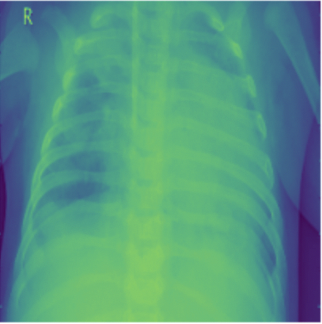

Pneumonia is an acute pulmonary infection which causes inflammation of air sacs called Alveoli. It is most common in underdeveloped or developing nations which have below average air quality and sanitation standards. Pneumonia can be of these three forms viral, bacterial or fungal which makes it airborne and contagious. It mostly effects children under the age of five or elderly people who have weak immune system [who]. Symptoms include coughing, fever, difficulty in breathing, loss of appetite etc. and is life threatening. COVID-19 induced Pneumonia has been a major reason for pandemic deaths in the world [stats]. Pneumonia is a rapid attacking infection whose quick diagnosis is important for saving lives. Detection of Pneumonia normally requires a highly skilled doctor to look at the Chest X-rays (CXR) and CT scans and requires medical history to arrive at a conclusion. Normally a foggy CXR with white spots are a few indicators of Pneumonia Fig. 1. This manual process might be expensive and critically time consuming. The recent advancements in Machine learning and Computer vision might prove really helpful in quick and accurate detection of Pneumonia and can potentially save a lot more lives especially during pandemics like COVID-19 which faced shortage of human expertise.